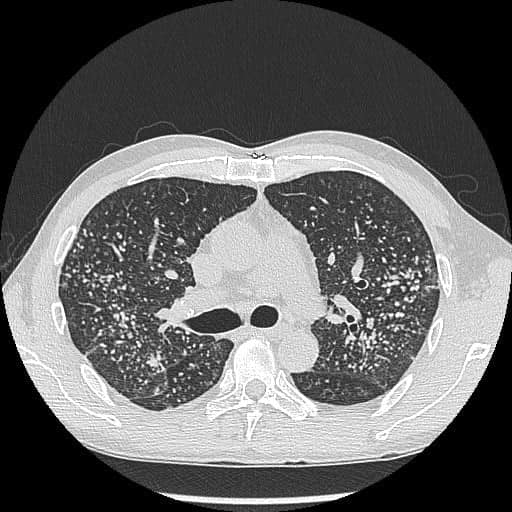

▲照X光发现,该男子长满肺结节,如“满天星”。(图片来源:“胸腔内科医生苏一峰”facebook专页)